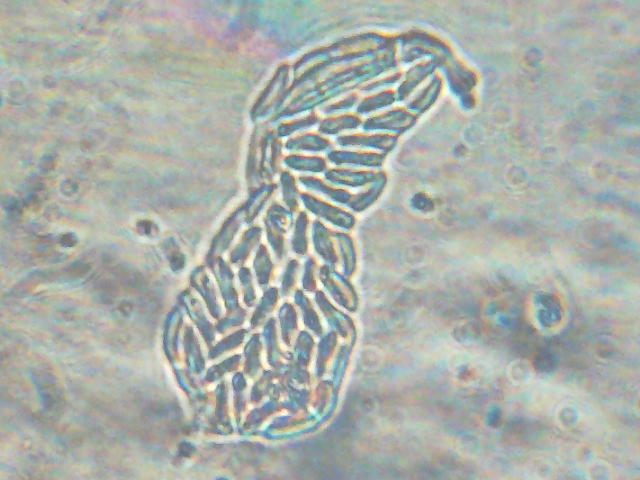

’Yás•a@•ª¶Žq